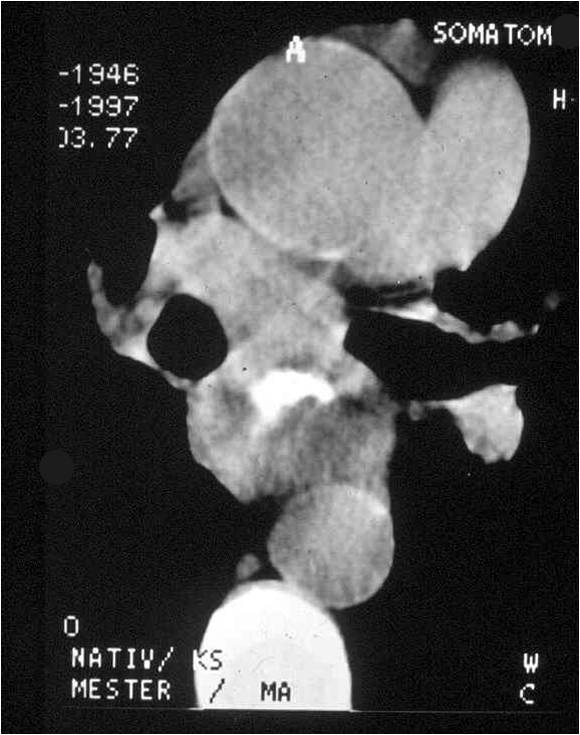

Colon diverticulosis:

One of the most common disorder of the large intestine, its frequency increases by age.

Clinical presentations: Patients can be symptom fee. If complicated with diverticulitis it can cause abdominal pain in the region corresponding to the affected bowel segment. Bleeding, perforation can occur.

Radiographic findings: multiplex round collections are seen on the sigmoid and descending colon.

Double-contrast irrigoscopy.

Image

Fig.23.: Radiographic image: multiple, round filling defects are seen on the sigma and on the descending colon.